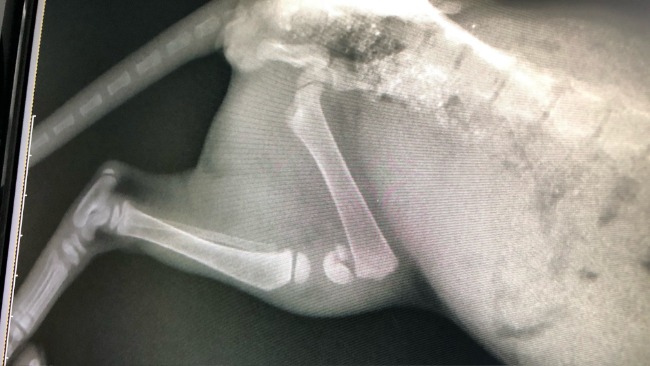

Po wizycie w gabinecie weterynaryjnym okazało się, że chłopak oprócz wycieńczenia, zapchlenia i zarobaczenia ma złamaną łapkę…

Koszt operacji to 1500 zł!!!

Zabieg musi odbyć się jak najszybciej, żeby kociak miał szansę zachować nóżkę, inaczej grozi mu amputacja.